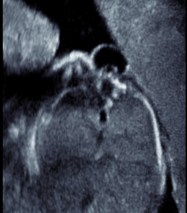

le diagnostic est souvent anténatal, l’échographie identifie une cavité kystique avec les radicelles nerveuses en son sein, une moelle abaissée non recouverte d’épiderme. dans d’autres cas (rachis mal vu en échographie), c’est la présence d’une hydrocéphalie anténatale qui fait rechercher et trouver le spina bifida.

la moelle est exposée (c’est la placode) au centre de la malformation, entourée d’une collerette d’arachnoïde, puis d’épiderme recouvrant la poche de dure-mère au sein de laquelle les radicelles relient la placode aux gaines radiculaires. le plan dermique adhère au plan dure-mèrien qui permettra de refermer la myéloméningocèle. si les membranes arachnoïdiennes sont ouvertes, il existe un écoulement continu de liquide cérébro-spinal qui atteste d’une hydrocéphalie communicante.